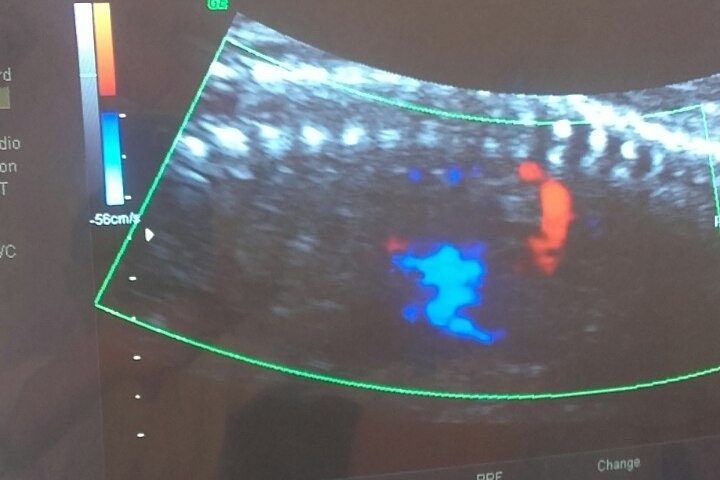

На глобално ниво, ракот на грлото на матката е четврт најчест рак кај жените, со околу 600.000 нови случаи во 2022 година. Истата година, околу 94% од 350. 000 смртни…